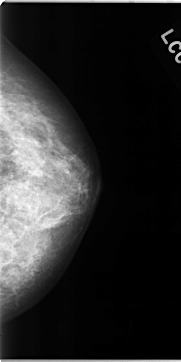

C_0127_1.LEFT_MLO

C_0127_1.LEFT_CC

LEFT_CC LINES 4696 PIXELS_PER_LINE 2352 BITS_PER_PIXEL 12 RESOLUTION 50 NON_OVERLAY

LEFT_MLO LINES 4712 PIXELS_PER_LINE 2416 BITS_PER_PIXEL 12 RESOLUTION 50 NON_OVERLAY